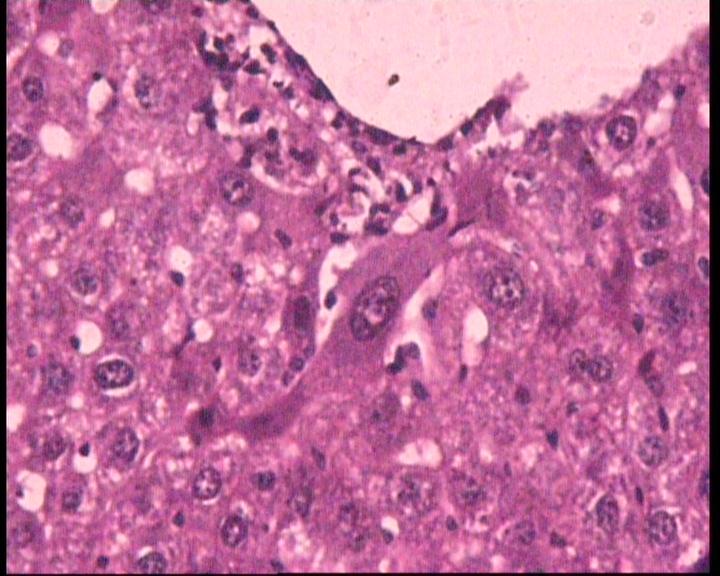

A significant (p<0.05) reduction in ALT levels (41.50 IU/l) in AMRME treated groups IV at the dose level of 250 mg/kg b. wt. Was observed, while at the higher dose level of 500mg/kg b. wt. the level was decreased to 31.69 IU/l in AMRME treated group V respectively in comparison to the silymarin - treated group III. However a non-dose dependency was observed in the AST levels in the groups treated with AMRME (IV, V) at dose level of 250 and 500 mg/kg b. wt. respectively. The result showed that AMRME was effective against the hepatic damage based on serum enzyme AST level. A significant (p<0.05) reduction in AMRME was observed in the glucose level from was 98.19 mg/dl to 81.55 mg/dl at the selected dose levels of 250 mg/kg b. wt. and 500 mg/kgb. wt. respectively in comparison to the with the CCl4- treated group II, however, these values were significantly (P<0.05) higher than in the silymarin- treated group III. A significant (p<0.05) reduction in the elevated serum cholesterol levels was observed 82.47 mg/dl and 67.70 mg/dl in the AMRME treated groups IV and V at dose level of 250 mg/kg b. wt. and 500 mg/kg b. wt. respectively in comparison to the CCl4- treated group II (117.31mg/dl) and silymarin - treated group III (89.81mg/dl). A significant (p<0.05) reduction in AMRME for total protein was observed in dose dependent manner at the selected dose levels of 250 mg/kg b. wt. and 500 mg/kg b. wt. The maximum reduction of total protein was 7.06 g/dl in AMRME at the higher dose level of 500mg/kg b. wt. in comparison to the standard drug silymarin treated group III (7.33g/dl). A significant (p<0.05) reduction in the bilirubin levels was observed in AMRME at the higher dose levels of 500 mg/kg b. wt. as indicated by the statistical values of 0.52mg/dl, in comparison to the standard drug silymarin (0.76mg/dl). At lower dose level of 250 mg/kg b. wt the statistical values for AMRME group IV was 1.05 mg/dl which indicated the dose dependent reduction of bilirubin. A significant (p<0.05) reduction in albumin levels from 4.53 to 4.36 mg/dl in the groups IV and V treated AMRME at dose level of 250 and 500 mg/kg b. wt. was observed in comparison to the CCl4- treated group II. The order of the reduction of the elevated level of albumin in a dose dependent manner is an indicative of effectiveness of AMRME towards liver protection. However a non-dose dependency was observed in the urea levels in the groups treated with AMRME (IV, V). The histopathological result of all the groups is shown in (Fig. 1 A & B). In CCl4 –treated group II, the liver exhibited severe vacuolar degeneration of the hepatocytes and loss of sinusoidal spaces (Fig. 1A). The liver from group III exhibited mild congestion of central vein along with mild vacuolar degeneration of hepatocytes (Fig. 1B).

Fig. 1: (A) Liver section of mice treated with CCl4 (negative control) × 7 days showing severe vacuolar degeneration of the hepatocytes and loss of sinusoidal spaces (B) Liver section of mice treated with CCl4+ silymarin dose (3 mg/kg. b. wt.) × 7 days showing mild congestion of central vein along with mild vacuolar degeneration of hepatocytes

In the lower dose group of IV (250mg/kg b. wt) of AMRME the liver in this group exhibited moderate congestion of large blood vessel and mild vacuolar degeneration in the hepatocytes and in high dose groups V (500 mg/kg b. wt) of AMRME the liver showed almost normal architecture.In this study, an increase in the levels of serum cholesterol, total proteins, urea, albumin, glucose, triglycerides and AST (aspartate aminotransferase), ALT (alanine aminotransferase) and urea were found in CCl4-treated mice indicating liver damage, although, these values were reduced significantly (P<0.05) in the silymarin, treated group.

Histopathological study also revealed that structural, changes such as severe vacuolar degeneration of the hepatocytes and loss of sinusoidal spaces were observed in the CCl4-treated group, whereas in AMRME treated groups at 250 mg/kg exhibited moderate congestion of large blood vessel and mild vacuolar degeneration in the hepatocytes whereas at 500 mg/kg b. wt liver showed almost normal architecture. From the results obtained it can be concluded that AMRME at 250 mg/kg and 500 mg/kg b. wt., following oral administration in drinking water produced a dose-dependent hepatoprotective effect in mice with CCl4-induced hepatotoxicity.